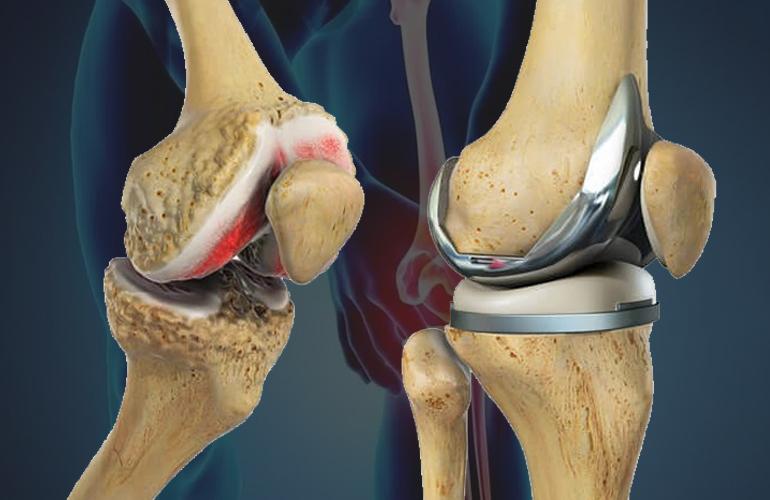

Indications for Total Knee Replacement -Severe os...

Total knee replacement (TKR) is considered necessa...